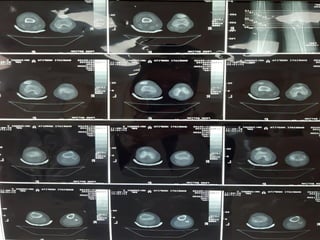

CT Scan

8

TT-TG:15 mm

Shallow

trochlea